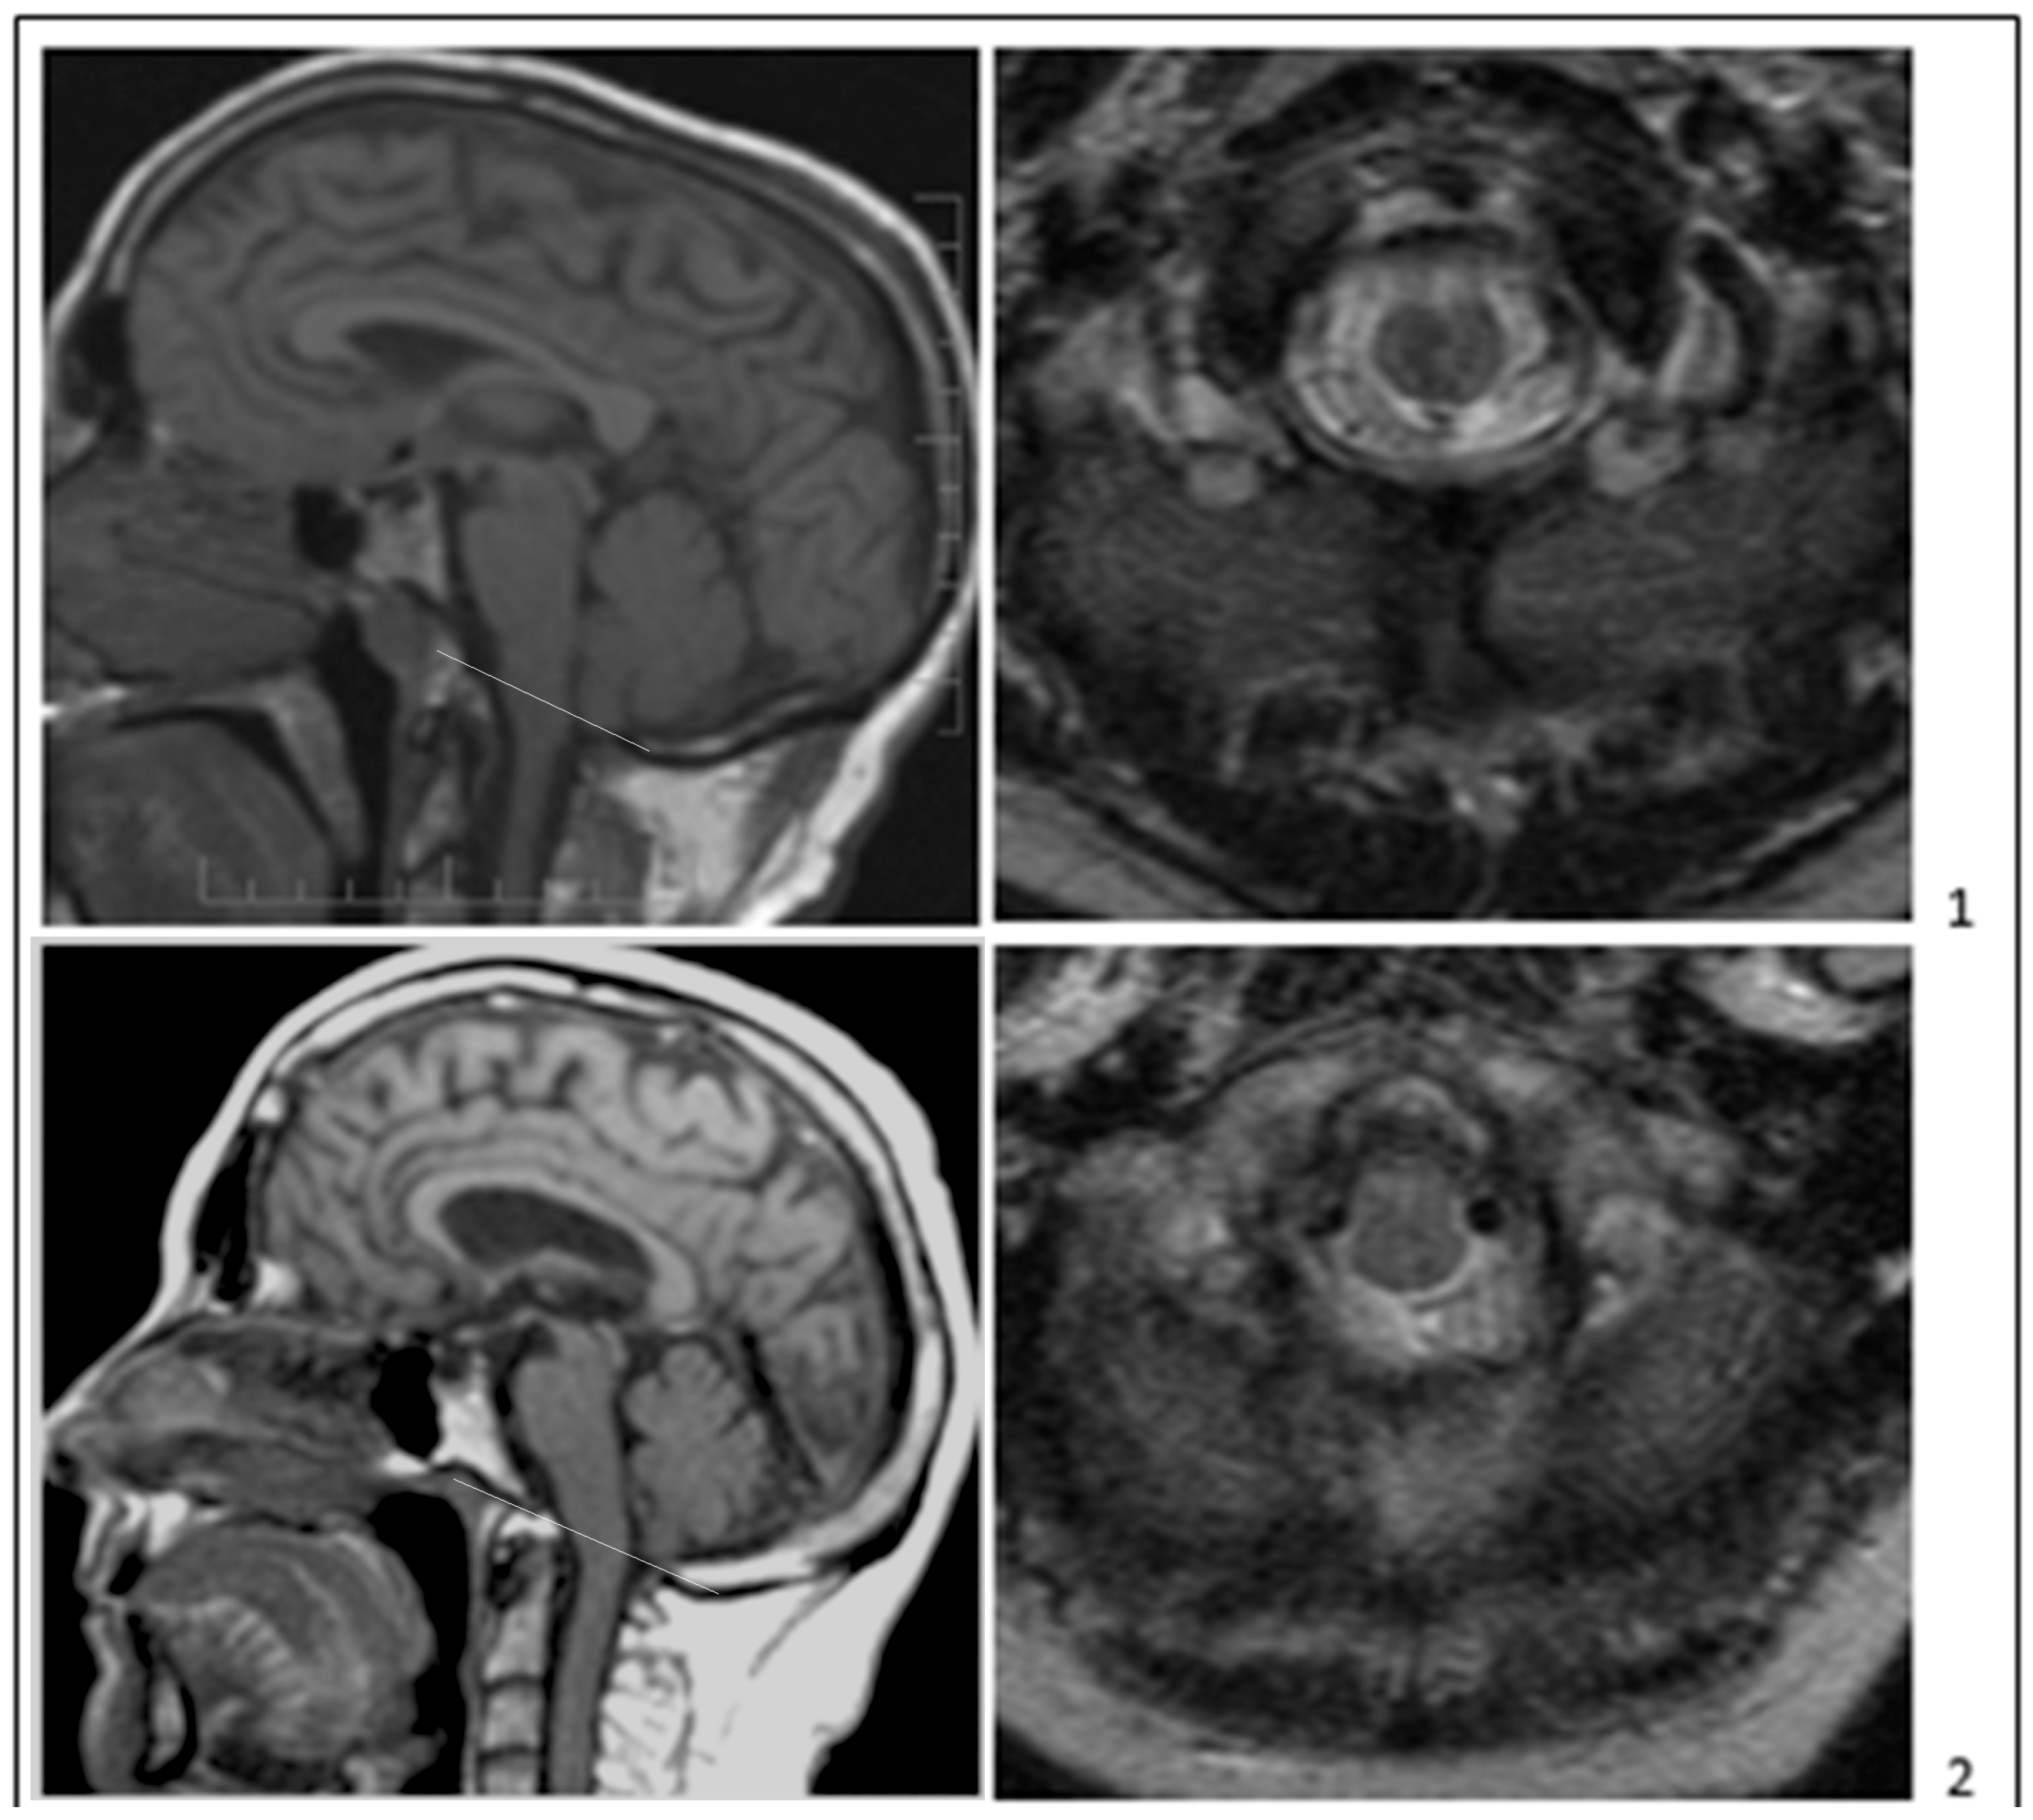

- Bogdanov, E.I.; Faizutdinova, A.T.; Heiss, J.D. Posterior cranial fossa and cervical spine morphometric abnormalities in symptomatic Chiari type 0 and Chiari type 1 malformation patients with and without syringomyelia. Acta Neurochir. 2021, 163, 3051–3064. [Google Scholar] [CrossRef]